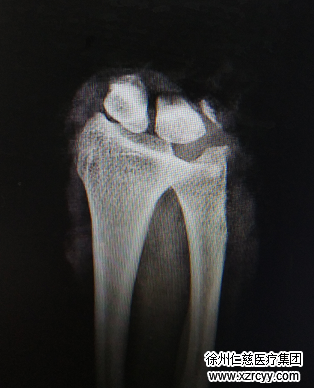

病人来到医院已经由于失血太多,全身湿冷,神情淡漠,经手外科三病区主治医生李刚诊断,赵阿姨右手腕离断,前臂血管、神经、肌腱损伤严重,右上臂肱骨骨折……

“啪——”手术室无影灯亮起,李刚医师手术小组争分夺秒,为患者实施“右手腕清创再植+右手、右前臂切开减压术”。手术中,医生先固定骨折断端,吻合动静脉让肢体通血,然后一一修复断裂的肌腱、肌肉及神经……知道最后一针缝合完毕,已经是第二天凌晨4点钟,经过近8个小时的努力,术中输血1600ml,手术成功!